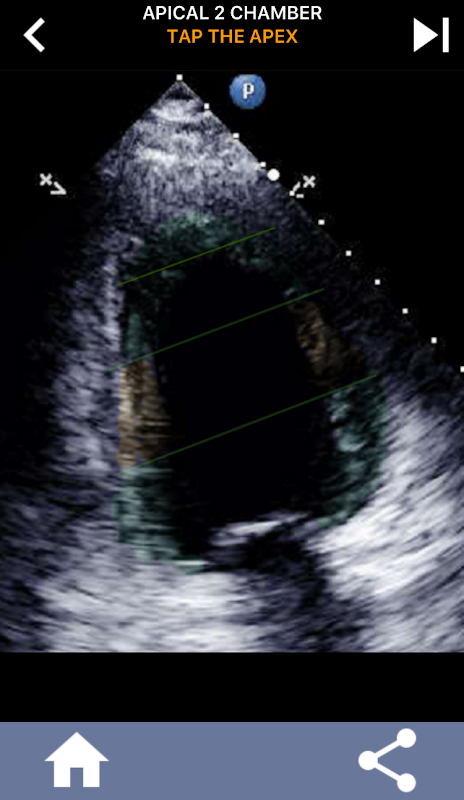

It is essential for ultrasound echocardiographers to learn the American Heart Association cardiac segmentation of the left ventricle into 17 segments which is the standard widely used by many other imaging modalities such as magnetic resonance imaging,cardiac nuclear tests, etc... to describe the location of affected segments and function. Many times the person reading your echo will ask " what did you see?" and replying with an exact location of the affected area is what is expected.

This app contains all the echo views showing the AHA segmented myocardium and will quiz you to tap the correct segment. I personally find that repetitive quizzing works best for me when I need to quickly learn/memorize subject. If you are an ultrasound student studying echo/TTE I think this would be an excellent complement to your studies.